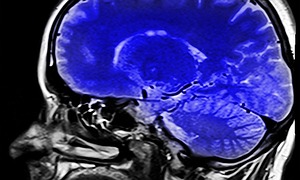

Die Vorstellung, dass geistige Fähigkeiten im Alter zwangsläufig abnehmen, hält sich hartnäckig im kollektiven Bewusstsein, obwohl sie wissenschaftlich längst widerlegt wurde. Professor Dr. Christian Gaser, Neurowissenschaftler und Direktor des Universitätsklinikums Jena, hat mit der Vallecas-Studie über 1000 Menschen im Alter von 80 Jahren und älter untersucht, um frühe Anzeichen kognitiver Beeinträchtigungen zu identifizieren.

Demnach verändern sich bestimmte Prozesse, die mit Denken, Erinnern und Wahrnehmen verbunden sind, etwa die Verarbeitungsgeschwindigkeit oder das Kurzzeitgedächtnis. Doch das Gehirn bleibt ein Leben lang lernfähig, anpassungsbereit und wach.

Was sich verändert, so der Experte, ist nicht die Fähigkeit zu lernen, sondern die Art, wie wir lernen. Ältere Menschen verfügen über ein reiches Erfahrungswissen, über ausgeprägte Mustererkennung und über die Fähigkeit, neue Informationen in sinnvolle Zusammenhänge zu bringen.

Die Neurobiologie spricht hier von "neuronaler Plastizität", der Fähigkeit des Gehirns, sich durch Nutzung zu verändern. Diese Plastizität bleibt erhalten, solange das Gehirn aktiv gefordert wird, durch Neugier, Kommunikation, Bewegung und sinnvolle Aufgaben.